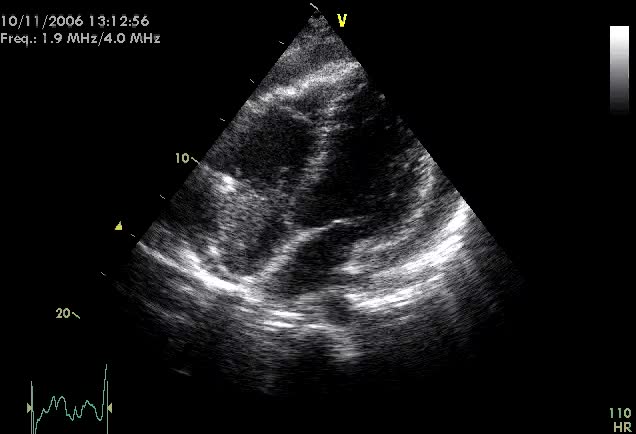

Vegetazioni su catetere

Giovanni Corrado